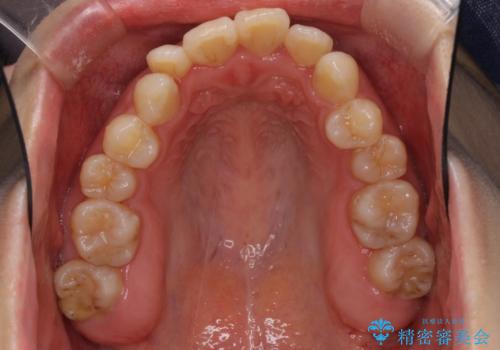

インビザラインによる矯正治療は、どれだけマウスピースを外す時間を短くできるかが成功の鍵となりますが、抜歯矯正ではよりシビアに要求されます。

こちらの患者様は、1日22時間以上を厳守してくださり、3年強で終えることができました。